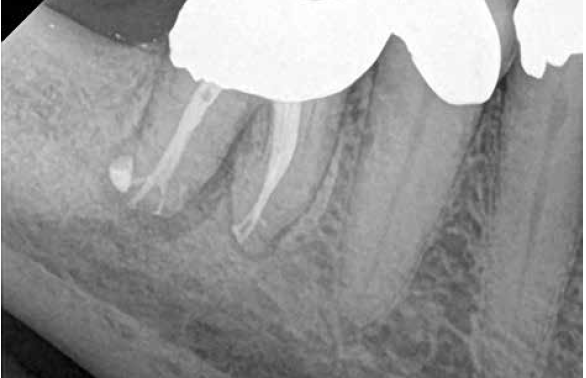

A body of research has emerged in recent years on the management of severe dental pain, exemplified by the diagnosis of an acute apical abscess where drainage cannot be achieved, symptomatic apical periodontitis, or irreversible pulpitis.11 An example of an acute apical abscess is depicted in Figure 1 and Figure 2. These conditions typically represent the most severe discomfort experienced by patients, and consequently, they serve as an excellent model for pain management. Treatment strategies for these issues and other painful conditions should include both definitive treatments for the diagnosed condition as well as adjunctive pharmacologic management.

(1.) A 74-year-old male presented with an acute apical abscess associated with tooth No. 30. The pre-operative periapical x-ray revealed evidence of apical pathology.

Figure 1

(2.) The infection was managed with oral antibiotics, root canal therapy, and a combination of ibuprofen and acetaminophen to manage the preoperative and postoperative discomfort.

Figure 2